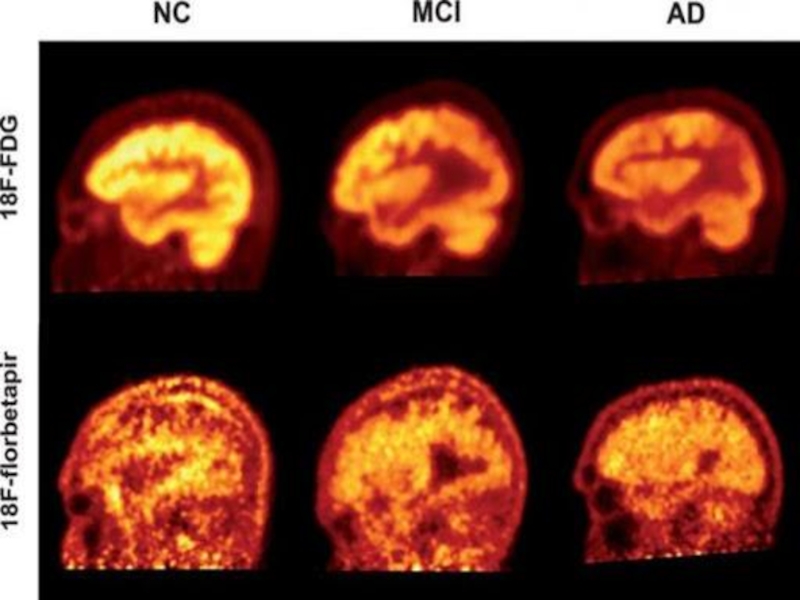

Слайд 24Достаточно большое применение нашла ПЭТ в диагностике и дифференциальной диагностике

нейродегенеративных заболеваний. К примеру, у пациентов с болезнью Альцгеймера происходит симметричное

снижение метаболизма коры теменно-височных областей, что указывает на патологии.

Диагностика нейродегенеративных заболеваний

Достаточно большое применение нашла ПЭТ в диагностике и дифференциальной диагностике нейродегенеративных заболеваний. К примеру, у пациентов с